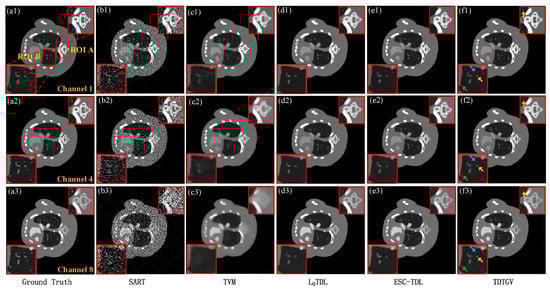

Figure 4 and Figure 5 show the images reconstructed using SART, TVM, L0TDL, ESC-TDL, and the proposed algorithm TDTGV at 160 and 80 views, respectively. In the figures, the three rows represent the reconstruction results of various methods for channels 1, 4, and 8. It can be observed from the figures that the proposed algorithm can achieve higher-quality images. Specifically, under the simultaneous sparse view and low-dose conditions, the reconstructed images obtained by the SART algorithm are contaminated by significant noise and obvious artifacts, resulting in the worst reconstruction performance, as shown in Figure 4(b1–b3) and Figure 5(b1–b3). The TVM algorithm improves the reconstruction results, but there is still a problem of image blurring, especially in high-energy channels, as shown in Figure 4(c1–c3) and Figure 5(c1–c3). The L0TDL and ESC-TDL algorithms improve the edge protection ability of the images to some extent; however, due to the instability of tensor dictionary training samples, the recovery ability of fine image structures needs to be improved, as shown in Figure 4(d1–d3,e1–e3) and Figure 5(d1–d3,e1–e3). Compared to the previous algorithms, it can be seen from Figure 4(f1–f3) and Figure 5(f1–f3) that the proposed TDTGV algorithm performs better in terms of image structure protection and detail recovery.

To facilitate a more detailed comparison of the reconstructed images, we selected two regions of interest (ROIs) in Figure 4 and Figure 5 and enlarged them to compare the reconstruction results further. The selection of ROIs is shown in Figure 4(a1) and Figure 5(a1), marked by red boxes labeled as regions A, B, C, and D, respectively. The enlarged results are displayed in the red boxes in Figure 4 and Figure 5. By comparing the reconstruction results of each algorithm in the enlarged ROIs, it is evident that the proposed algorithm can successfully recover more small image structures, as indicated by the arrows, further verifying the advantages of the proposed algorithm.

Figure 4. Images representing a thoracic model of mice reconstructed from 160 projections using different methods: (a1a3) Ground Truth, (b1b3) SART, (c1c3) TVM, (d1d3) L0TDL, (e1e3) ESC-TDL, and (f1f3) TDTGV. From top to down, the display windows are [0, 0.25] cm−1, [0, 0.1] cm−1, and [0, 0.06] cm−1, respectively.